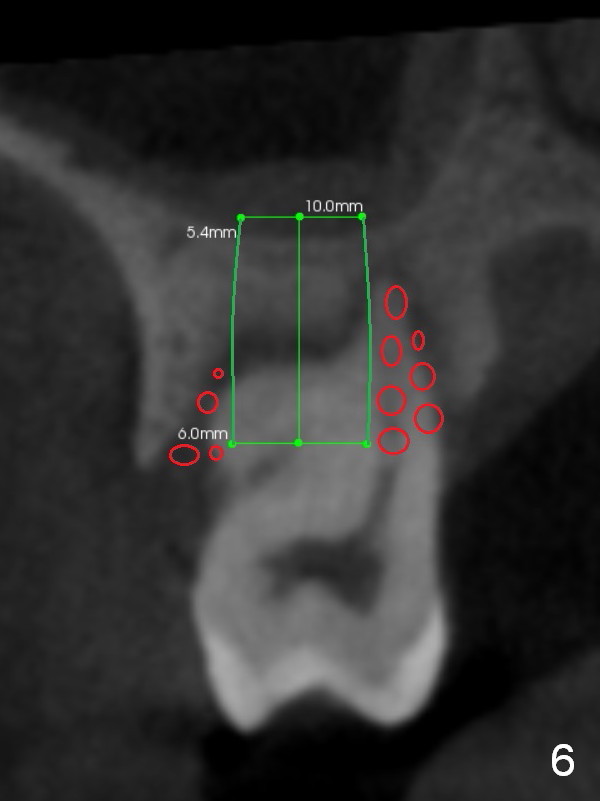

The socket is wider buccopalatally (Fig.2 (3-D disto-occlusal view),3 (coronal section)) than mesiodistally (Fig.1,4 (sagittal section),5 (axial section)). Unless more bone loss has occurred in the last year, a 6x10 mm UF implant is to be placed in the middle of the socket (Fig.6, (soaked with 2% Xylocaine/1:50,000 Epinephrine gauze)) with bone graft to be placed in the buccal and palatal gaps (red circles). Bone density in the middle of the socket is 550-700 Hounsfield units. Use RT2 or 2 mm pilot drill to start osteotomy ~ 3 mm. The largest osteotome is RT4, or largest reamer 4 mm, followed by 4.5x17 mm tap at 14 mm, until 6x17 mm one. Make sure that the sinus floor is penetrated.